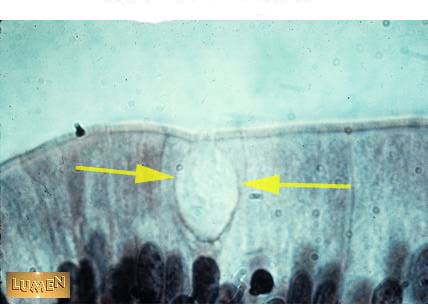

What kind of cell is this?

Goblet